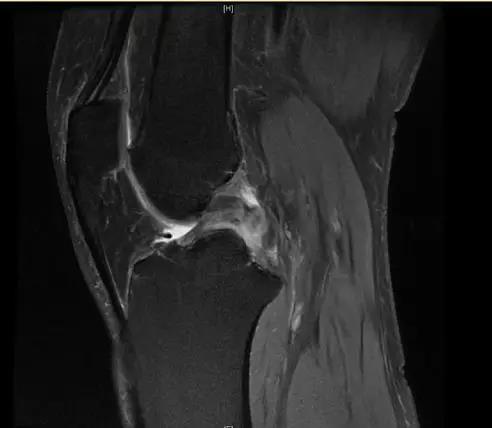

【有声病例】后交叉韧带断裂